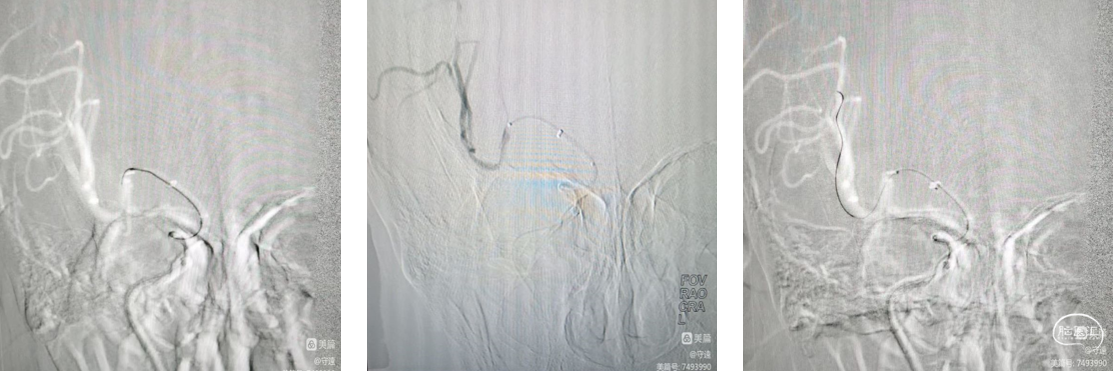

查体:BP:158/78mmHg,烦躁,不完全混合型失语,查体不合作,心律齐,四肢肌力不肯定,四肢无自主活动,双侧巴氏征阳性。造影示:基底动脉闭塞。

1、全麻下桡动脉入路:利用超滑导丝交换技术直接送入5F中间导管(下图1)。

2、中间导管到位造影基底动脉闭塞,向左侧椎动脉返流(下图3)。

3、微导管造影:微导管位于真腔,右侧大脑后动脉P3段(箭头所指)闭塞(下图2、4)。

4、支架释放:4*20取栓支架送入后可见血流通畅,左侧大脑后动脉仍闭塞。取栓后基底动脉通畅大脑后动脉P3段闭塞(下图5)。

决定取栓,微导丝通过,少量血流通过,血栓(箭头所指)更加明显了,回撤支架后造影:血流通畅,血管痉挛解除。

对于本次病例直接中间导管建立通路,中间导管到位造影基底动脉闭塞,4*20mm支架基底动脉取栓,小支架3*15mm大脑后动脉钳夹取栓。3*15mm小支架对血管刺激性更小,取栓术后血流通畅,未出现与支架相关并发症,且一把拉通,是远端血管取栓的一个选择。